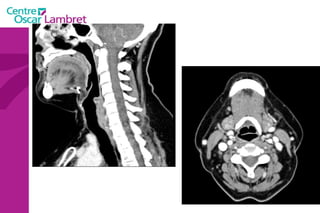

C 4 oes. Trachée Cordes vocales épiglotte

La  Trachée :  Comprise entre l'extrémité inférieure du larynx et l'origine des bronches. La paroi antérieure est en forme de fer à cheval ouvert en arrière. Cette paroi est constituée d'anneaux cartilagineux reliés par des lames fibreuses.  La paroi postérieure est plane, fibromusculaire. Elle divise au niveau de la cinquième vertèbre thoracique en deux bronches souches gauche et droite (sa division se nomme la Carène).  L’appareil respiratoire